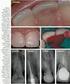

53 Reabsorción idiopática externa Procesos reabsortivos Es aquella que reabsorbe desde la superficie del cemento hacia la porción interna del diente, pero preservando la pulpa.

54 Reabsorción idiopática externa Procesos reabsortivos Características clínicas y radiográficas Imagen radiolucida a nivel radicular que puede proyectarse sobre el conducto radicular o no. Más frecuente en la porción media o apical de la raíz. A veces puede involucrar la región cervical.

55 p v

56 p v

57

58

59